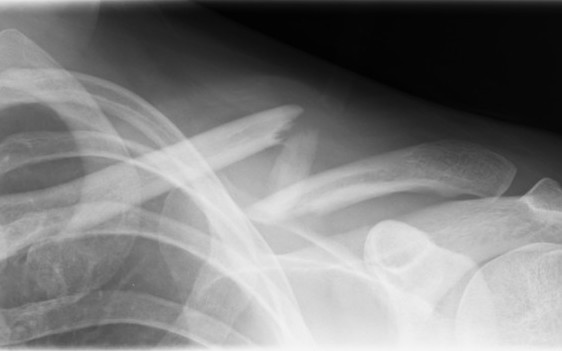

Compound clavicle fracture

Shorted / displaced midshaft clavicle fractures

Z shaped midshaft clavicle fracture